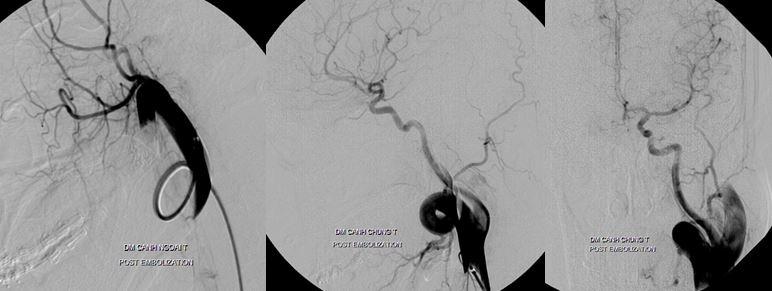

Cô gái trẻ ù tai trái từ nhỏ do rò động tĩnh mạch cảnh ngoài lưu lượng cao

Bệnh nhân nữ 22 tuổi vào viện có khối phồng đập vùng góc hàm trái, ù tai trái từ nhỏ, ngày càng lớn dần, chóng mặt tư thế… Bệnh nhân do một bác sĩ phẫu thuật mạch máu chuyển qua BS Trần Chí Cường, nhờ can thiệp nội mạch.

Rò động tĩnh mạch cảnh ngoài lưu lượng cao

Kỹ thuật dùng bóng kiểm soát dòng chảy và gây tắc

Bệnh nhân khỏi hoàn toàn sau can thiệp

Một trường hợp khác được BS Trần Chí Cường can thiệp năm 2007 là một bé gái 14 tuổi, thường xuyên bị đau đầu, ngất xỉu khi gắng sức, động kinh toàn thể trong thời gian dài không được chẩn đoán và điều trị dị dạng thông động tĩnh mạch não bẩm sinh.

Dị dạng thông động tĩnh mạch não bẩm sinh AVM-AVF

Trường hợp này khiến BS Cường phải suy nghĩ nhiều đêm, cuối cùng tìm ra phương pháp double catheter, giống như “đắp đập” từ từ để giảm dòng chảy. Kỹ thuật này sau đó đã được áp dụng điều trị thành công cho nhiều bệnh nhân khác, BS Cường cũng báo cáo với thế giới và được ghi nhận là một kỹ thuật can thiệp nội mạch thuộc bản quyền của bác sĩ Việt Nam, được các nước học hỏi.

Hình ảnh DSA thực hiện kỹ thuật double catheter